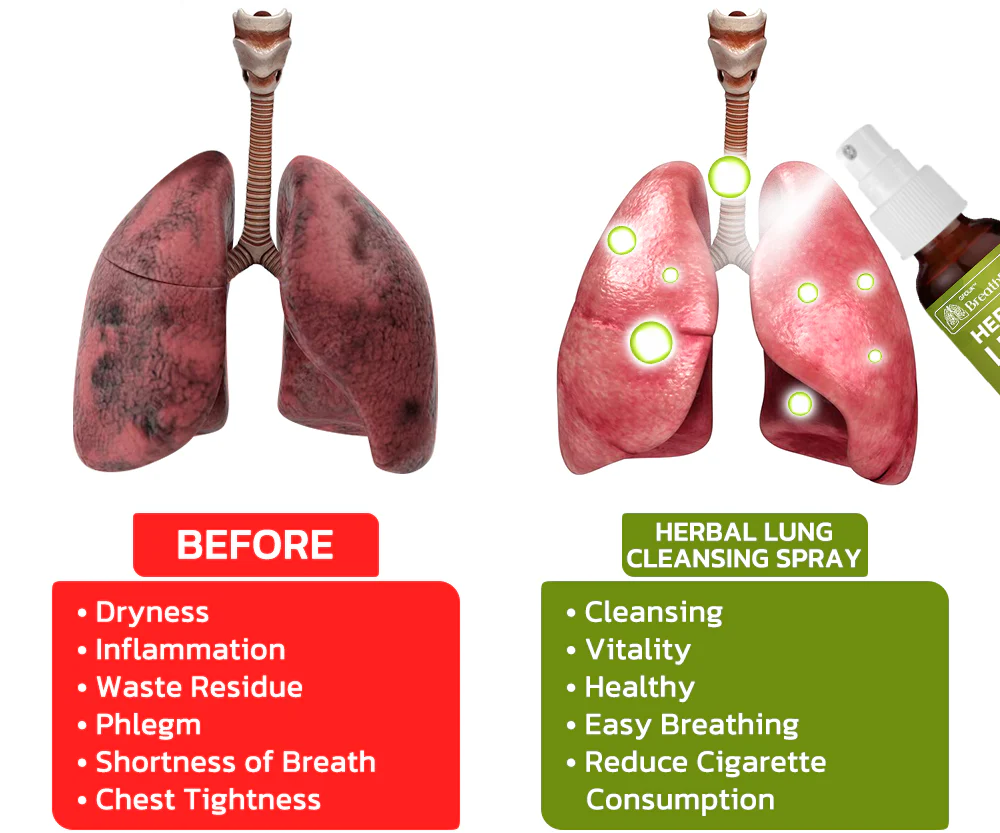

The HZA™️ BreathDetox Herbal Lung Cleansing Spray offers a convenient and effective solution for clearing mucus and waste from the lungs, as well as purifying and cleansing the upper respiratory passages. It is specifically designed to repair damage caused by allergies, asthma, dust, and smoking within a span of 8 weeks. This innovative product provides individuals with weakened respiratory systems an effortless opportunity to restore their breathing capacity.

【Expert】Organic Herbal Fusion – Purify trachea and lungs by eliminating lingering buildup – Restore optimal functionality of alveoli – Regenerate tracheal tissue – Alleviate allergies and asthma symptoms – Enhance the sensation of unobstructed breathing – Provide support for individuals with COPD

Dr. Kazzy’s research team has recently introduced the revolutionary HZA™️ BreathDetox Herbal Lung Cleansing Spray, presenting a groundbreaking solution for addressing allergies triggered by stress. This innovative spray is specifically designed to provide relief by applying it to the mouth, utilizing carefully chosen plant extracts. These natural ingredients work harmoniously to alleviate allergies and boost the respiratory system’s inherent ability to eliminate waste and mucus from the lungs. By fostering optimal lung health and function, this spray offers a holistic approach to sustaining respiratory well-being.